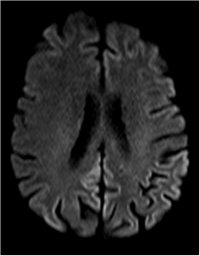

Creutzfeldt-Jakob - T2 - axial

Typische kortikale Signalsteigerung in der Diffusionwichtung.